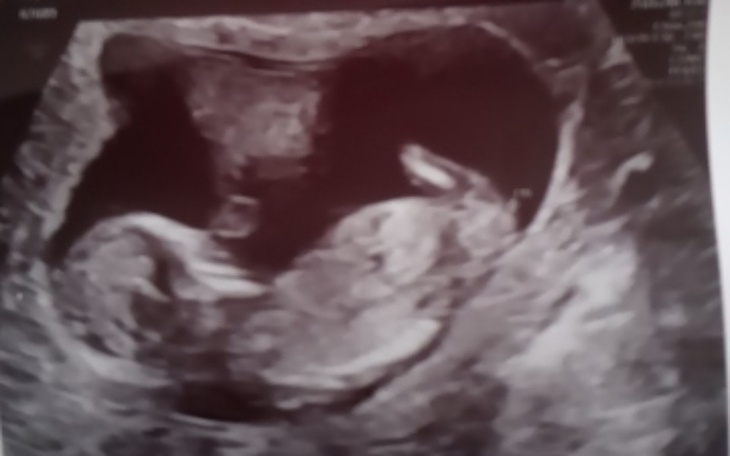

nazywam się Bartek. Wraz z dziewczyną spodziewamy się dziecka mieszkamy obecnie w kawalerce z której właścicielka chce nas wyrzucić ponieważ nie chce dzieci w mieszkaniu. Szukamy mieszkań lecz kaucję i czynsze przerastają nasze możliwości. Dziewczyna nie pracuje ponieważ jest w ciąży zagrożonej i wysiłek fizyczny może spowodować że poroni i dziecko umrze czego bym nigdy sobie nie wybaczył. Nie zarabiam kokosów lecz jako tako żyjemy chodź za 28m kawalerkę płacimy 2400 zł chcemy się z tąd wynieść więc prosimy o pomoc w uzbieraniu danej kwoty by móc żyć spokojnie i by dziecko miało komfortowe warunki do życia, przede wszystkim ogrzewanie którego obecnie w mieszkaniu nie mamy chodź właścicielka zapewniała nas że jest podłogowe po czym przyniosła nam grzejnik na prąd.